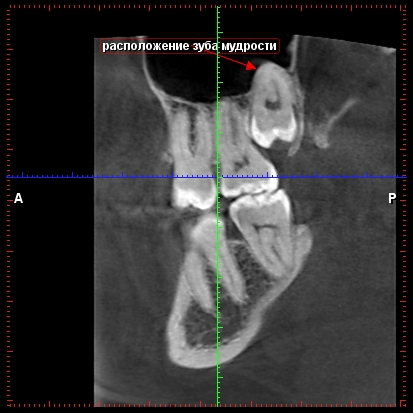

Hely bölcsességfog gyökerei az arcüreg